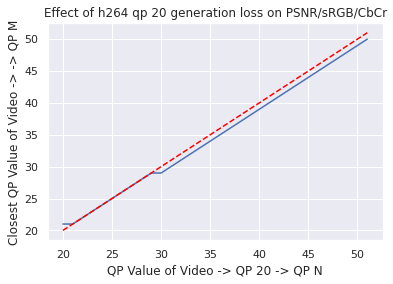

Data: As in [9], our colonoscopy video dataset was collected from screening colonoscopy procedures performed in three hospitals. We used a detector trained on a 16K video subset of the dataset, and we computed our classical codec analyses on a different 80 video subset (2.2M frames, 15K polyp frames). All videos and metadata were deidentified according to the Health Insurance Portability and Accountability Act Safe Harbor. Ground truth polyp labeling was provided by the gastroenterologist annotators described in [9]. The annotators were paid on an hourly basis, and pay was not based on the results they provided. The videos were compressed using H264 QP20 when transmitted from the hospitals. To justify our analyzing already-compressed videos, we used a small number of lossless videos to investigate the impact of re-compressing compressed videos to QP (so called “generation loss"). We found that the impact was negligible (see Appendix for details).

Since our dataset was compressed to be transferred from hospitals, we first investigated the impact of multiple stages of compression ("generation loss"). We used lossless video (24 seconds, 1.4GB) collected from an endoscope viewing dyed, non-human tissue. This gave the video the motion and texture characteristics of a colonoscopy. We then compared video quality between two compression schemes: compressing using H264 QP , where , and compressing to H264 QP20, then to H264 QP (when referring explicitly to this comparison, we will concisely refer to the latter as ’QP’). We then compared the average frame quality between these two schemes using two quality metrics (see ’Metrics’ section). The quality differences between these two compression schemes was minor in terms of PSNR-CbCr, which justifies our working with video data already compressed by H264 QP20.

See Figure 4 for compression quality as a function of QP value instead of compression rate, as well as quality measured by PSNR-Y. Furthermore, the Kolmogorov-Smirnov tests on PSNR-Y show the same behavior: treating each QP value separately, a two-sided between distributions shows that the frame quality is lower for polyp frames than for all frames (for each QP value, , , H264 PSNR-Y max p-value is , mean test statistic , HEVC PSNR-Y maximum p-value over all tests is , mean test statistic ). This result holds for each QP value between 20 and 51.